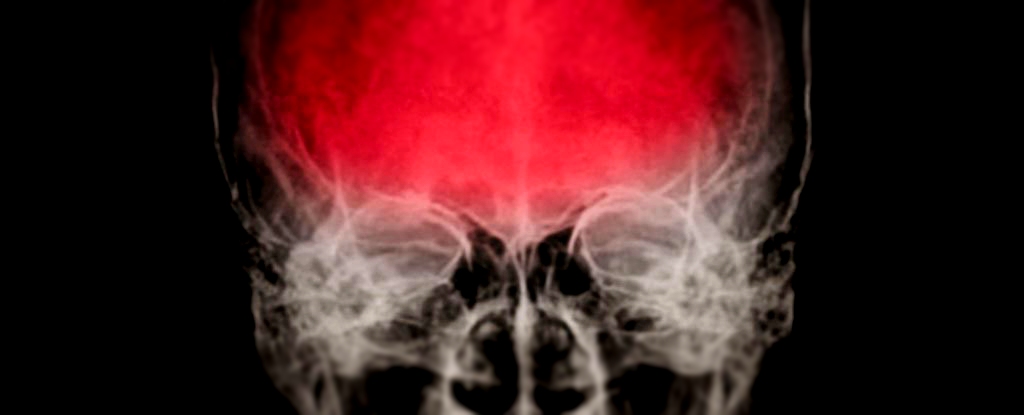

A serious knock to the head may also deliver an insidious blow to the human immune system – a one-two punch that could reawaken dormant viruses in the body, potentially contributing to neurodegenerative disease. A study using stem cell ‘mini brains‘ has shown that a herpes simplex virus 1 (HSV-1) infection already ‘arrested’ by the […]